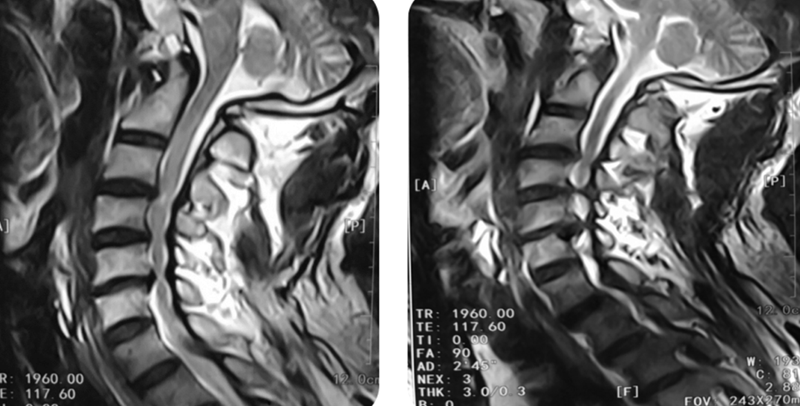

MRI:C3-4后方可见脊髓高信号改变

CT:C5-6